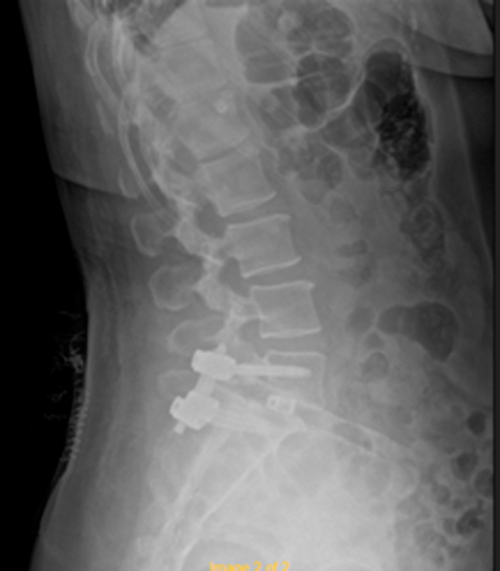

DIAGNOSI:

SPONDILOLISTESI CON STENOINSTABILITA’ L3-L5

Radiografia lombare pre-operatoria

Intervento chirurgico eseguito:

Artrodesi lombare mediante viti transpeducolari L3-L4-L5 + introduzione di cage intersomatica plif

Radiografia post-operatoria